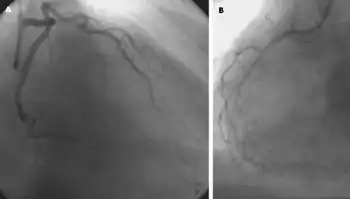

Dobutamine infusion (with radionuclide myocardial perfusion imaging) for detection of myocardial ischemia in a stress test

The drug is also commonly used in the hospital setting as a pharmacologic stress testing agent to identify coronary artery disease.